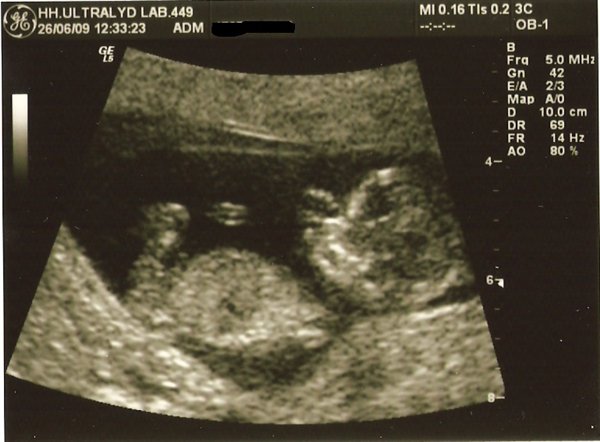

Jeg var til nf i dag! iih, hvor var det spændende og dejligt at se den lille.

Alt så fint ud og synes at billederne blev rigtig flotte

Terminen blev rykket et par dage fra 10.01.10 til 06.01.10, så er 12+2 uger henne

Vi har ikke fået svar fra doubletesten endnu, så har ikke fået endeligt svar.. Men udfra skanningen så alt fint ud, husker ikke helt, men det var ca. 1:5700, så det var SUPER.